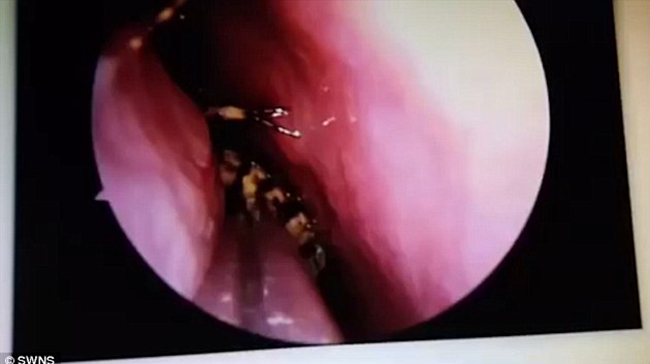

Kết quả siêu âm cho thấy, con gián đang nằm trên nền sọ, vị trí giữa hai mắt. Dù đã trú ngụ ở đó một thời gian nhưng nó vẫn sống.

Để gắp được con gián ra khỏi hộp sọ của người phụ nữ, các bác sĩ đã phải sử dụng tới máy hút và nhíp trong ca phẫu thuật kéo dài 45 phút đồng hồ.

Con gián đã chui được vào gần não của người phụ nữ.